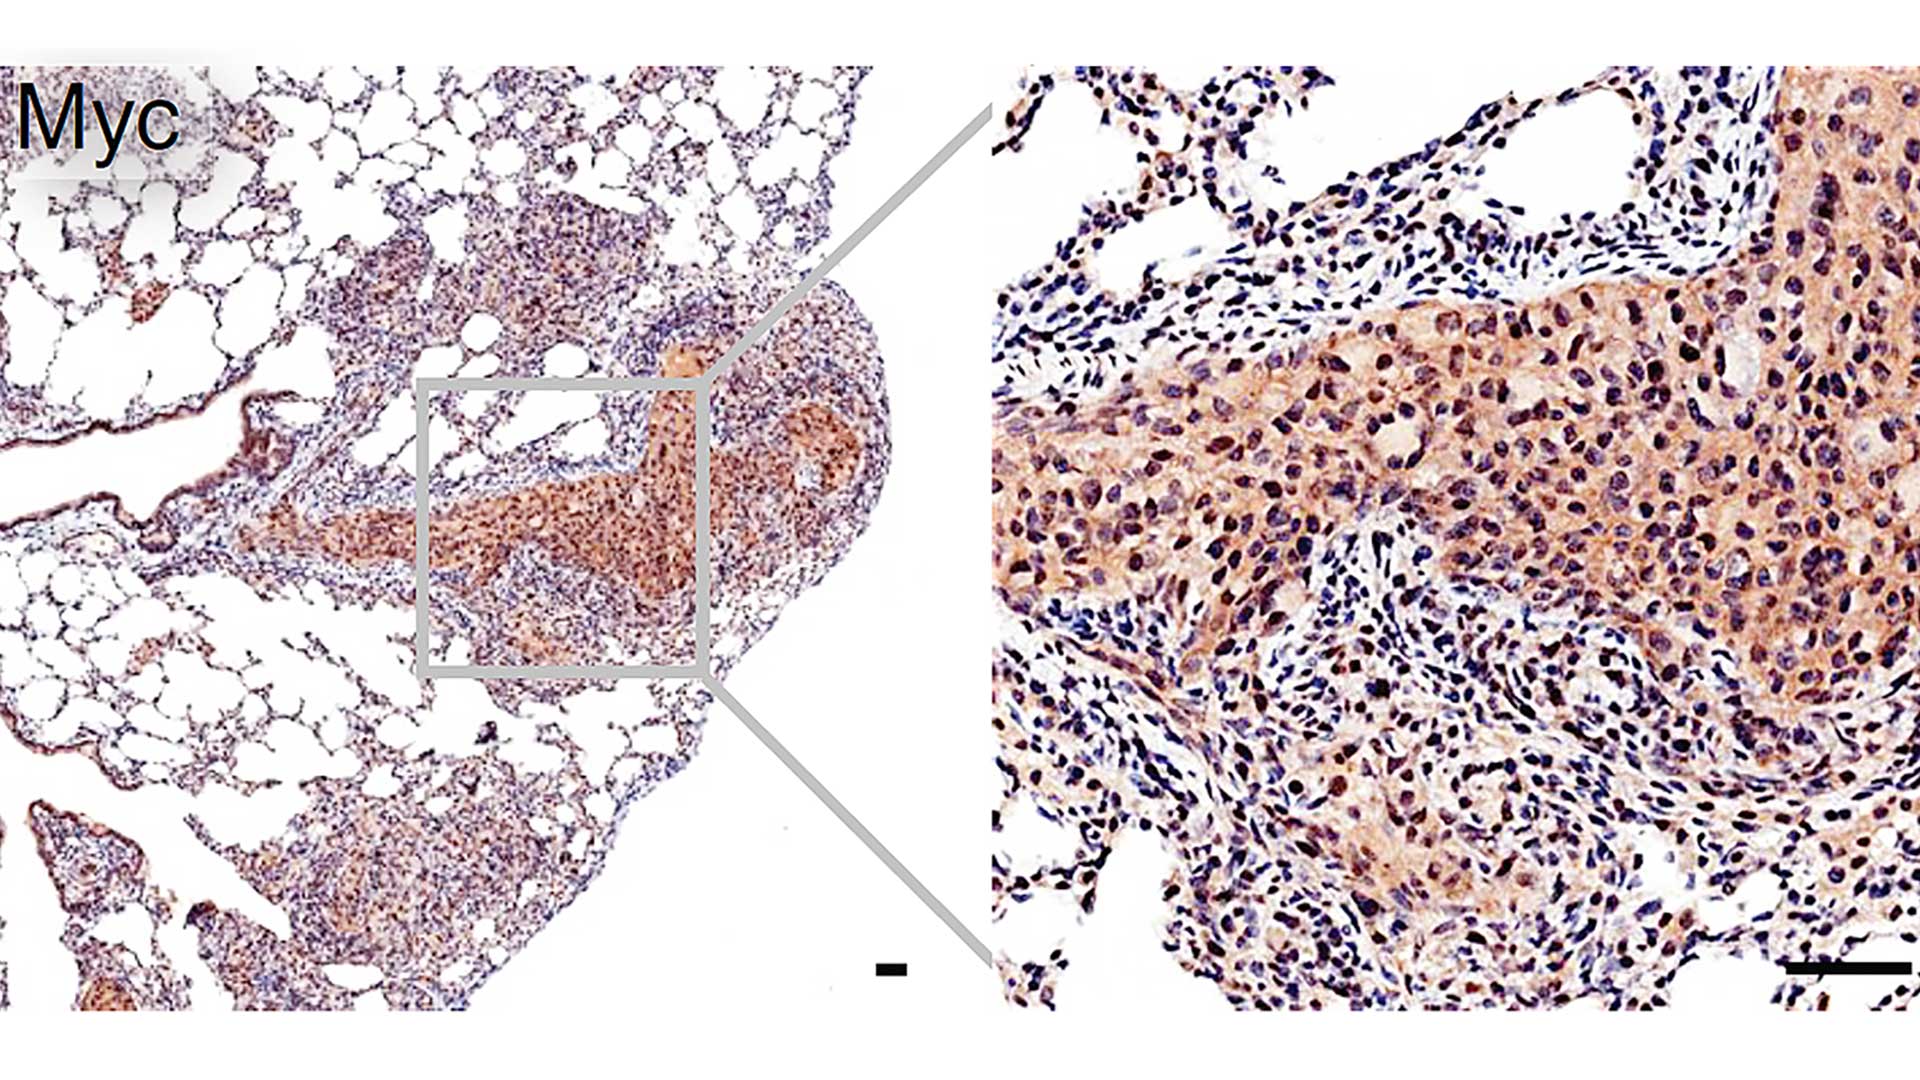

CSHL Professor Lloyd Trotman and his team discovered that a Vitamin K supplement called menadione slows prostate cancer in mice. Their research sets the stage for potential pilot studies in human patients that may lead to new and effective prostate cancer therapies.